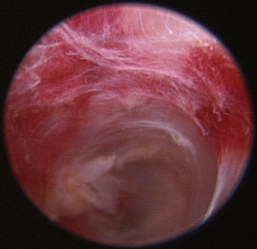

Normal turbinates have a smooth, pink-to-white surface and a spatial alignment that provides channels for the passage of air. The color varies and appears tan in the caudal nasal cavity. Turbinates come in different shapes and sizes, but the surface should be smooth. Ethmoid turbinates in the caudal nasal cavity will have a characteristic stippled or corrugated appearance (Figures 19-13 through 19-16). Ulcerations or various proliferations of the mucosa are indicative of disease. These changes are typically diffuse and accompanied by a lot of mucus. Mucus can be thin to purulent. Copious amounts can be flushed out of the nasal cavity to allow better visibility. The specific disease is determined by biopsy. After full examination of the nasal cavity, run the scope along the floor of the nasal sinus to the level of the choanae. Keeping the scope pointed in a ventral medial direction prevents inadvertent trauma or penetration of the cribriform plate. The index finger of the free hand can be used to follow the scope as it moves caudally over the hard palate; the surgeon can then palpate the scope through the soft palate when it moves into the nasopharynx. Some force is needed to complete this procedure and may result in increased bleeding.

image

Figure 19-16 Normal canine ethmoid turbinate.